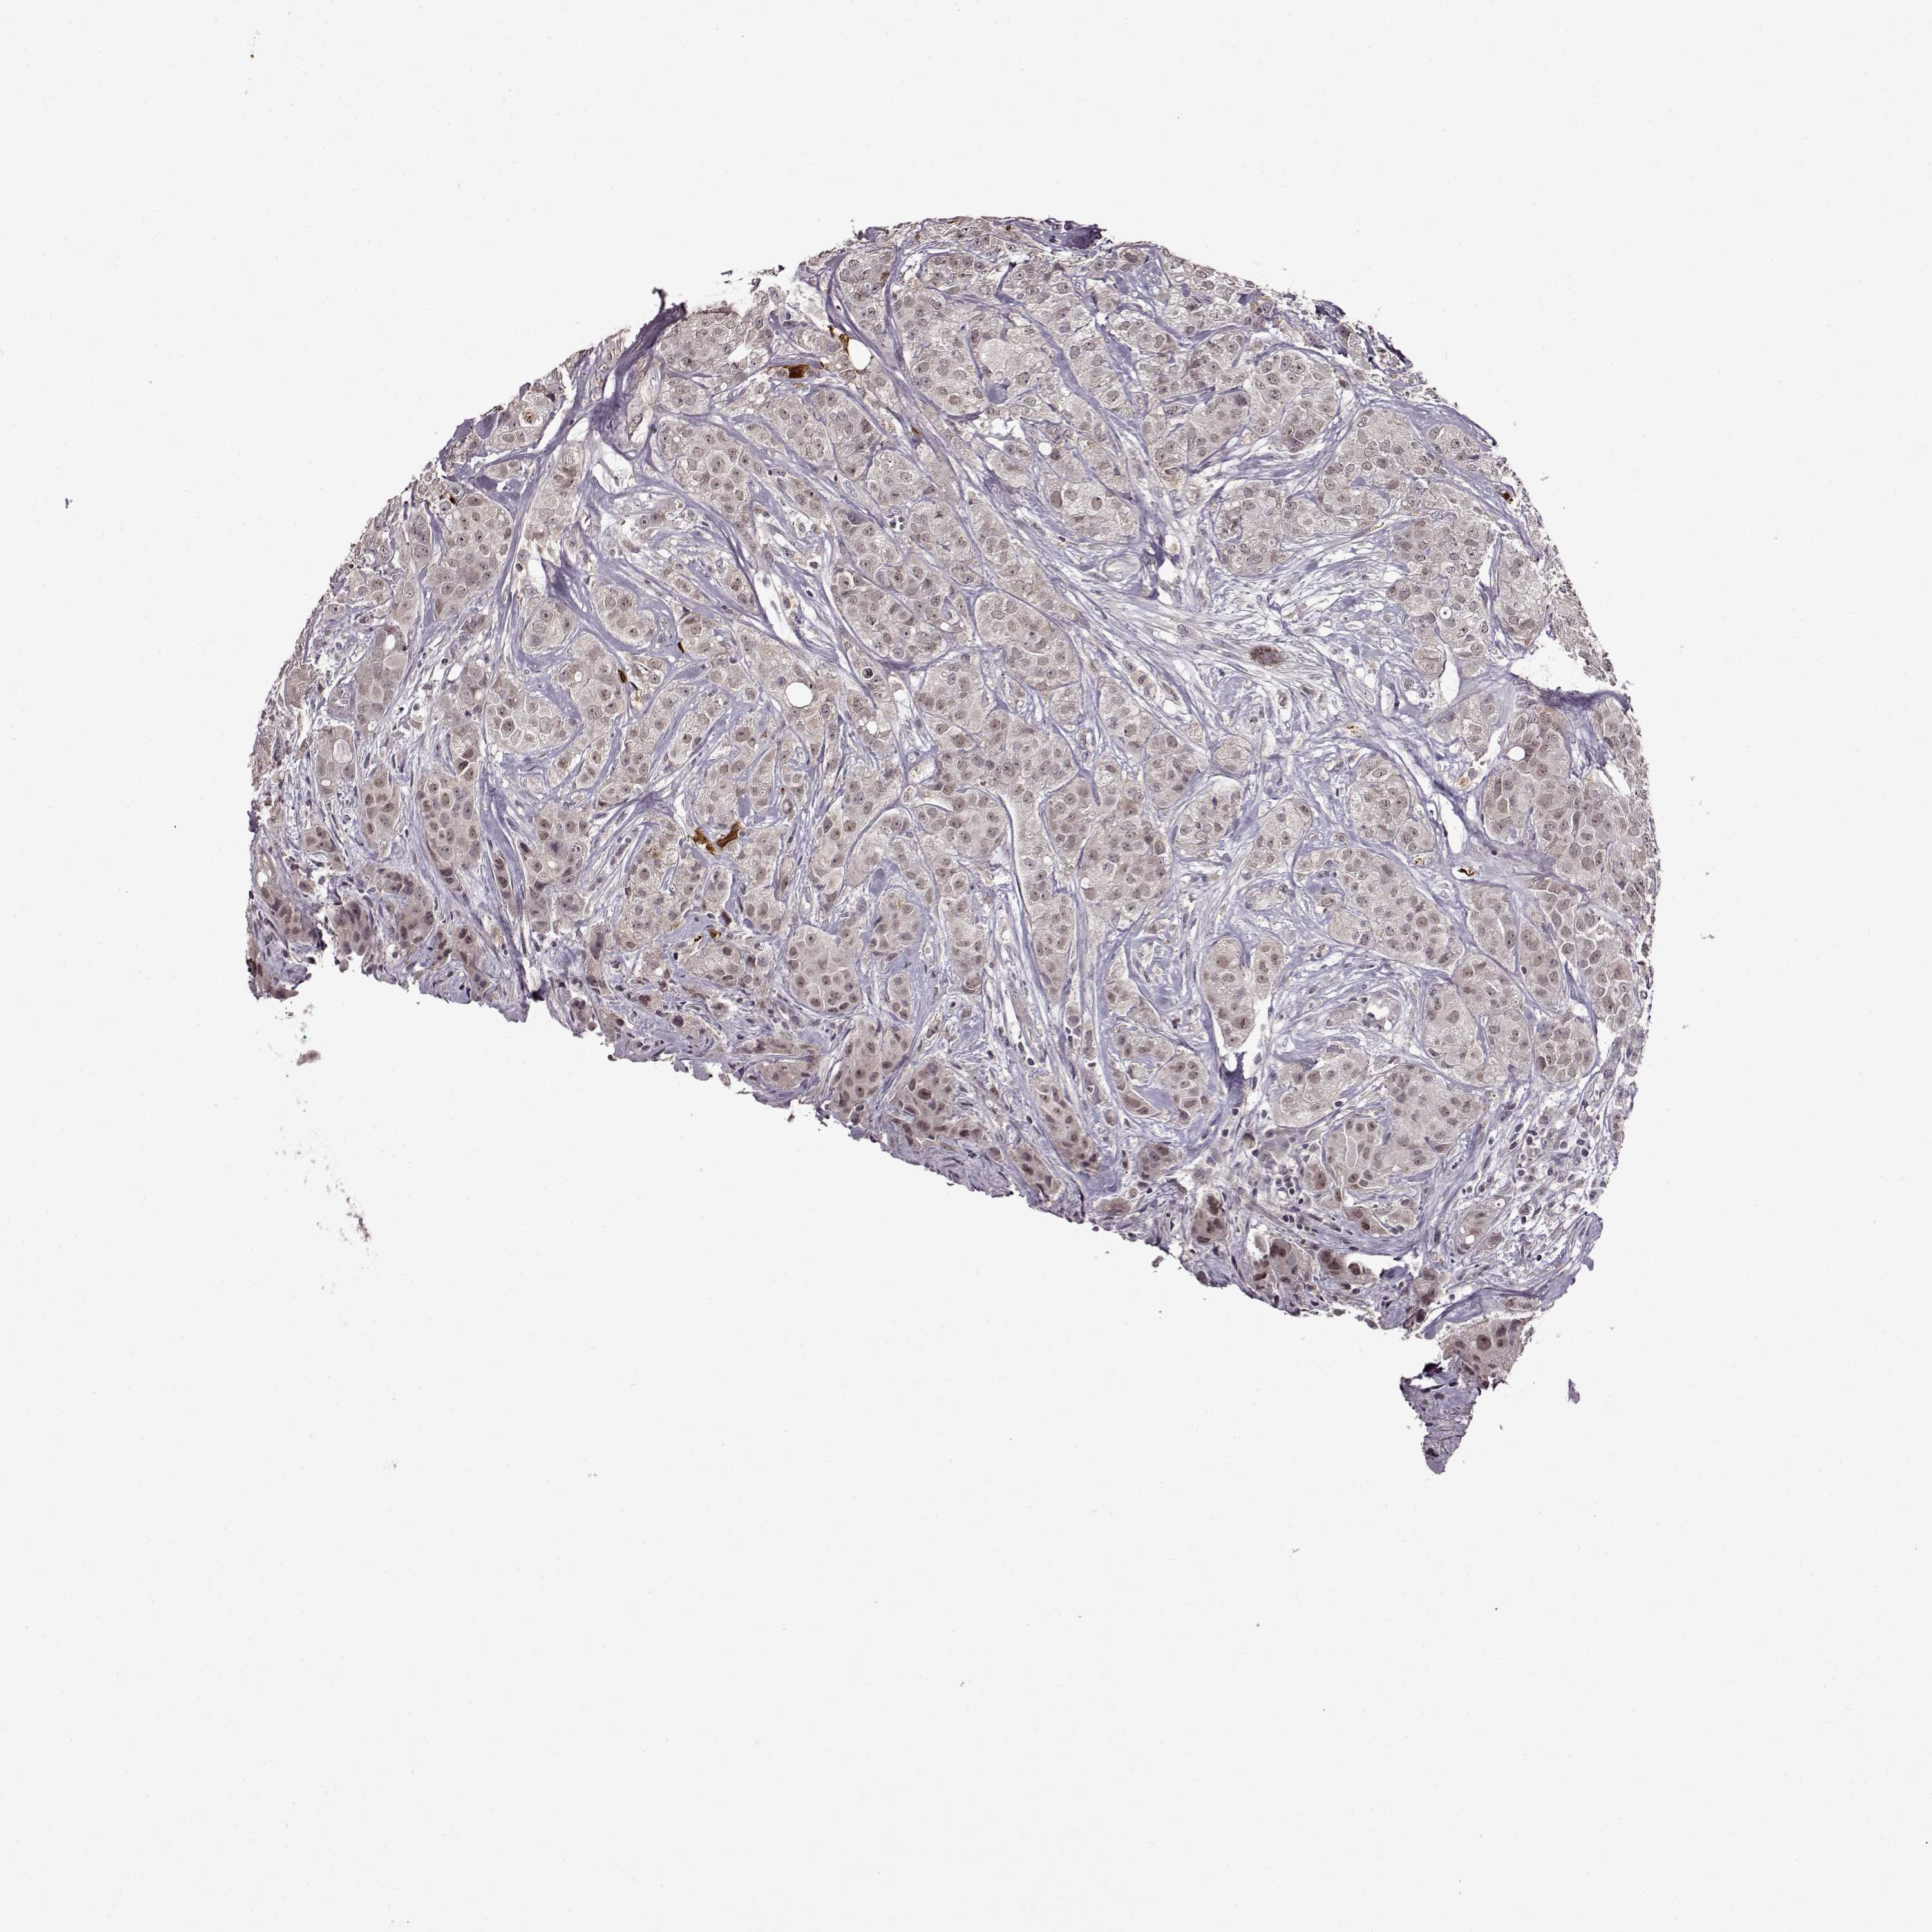

CANCER BREAST CANCER Show tissue menu

BRCA TCGA BRCA VALIDATION PROTEIN EXPRESSION